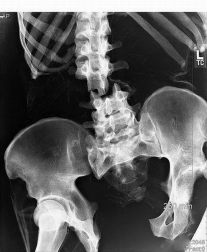

Este fin de semana foron un total de 12 persoas as ingresadas por lesións sufridas ao realizaren este baile de moda. O máis grave o de Alberto N. F. que foi trasladado de urxencia ao hopital lucense Lucus Augusti por unha fractura múltiple de cadeira ao levar ao extemo un baile xa de por si peligroso.

Alberto, que estaba a practicar o twerking con outros amigos e amigas, deicidiu tentar unha nova velocidade de balanceo da súa pelve coa mala sorte de que esa axitación rematou por romper a súa cadeira por diversos puntos.

Desde o Sergas informan que o paciente será operado para introducirlle unha nova cadeira de Titanio, que segundo apuntan permitirá nun prazo de entre 6 a 8 meses volver a bailar twerking con relativa normalidade. A nova cadeira cofinanciada pola UE contará cun sistema hidraúlico que permitirá moverse a velocidades imposibles para a xente do común, e que convertirán a Alberto no primeiro home biónico en bailar twerking. Ou como xa lle chaman na Fonsagrada o Twerkinator.